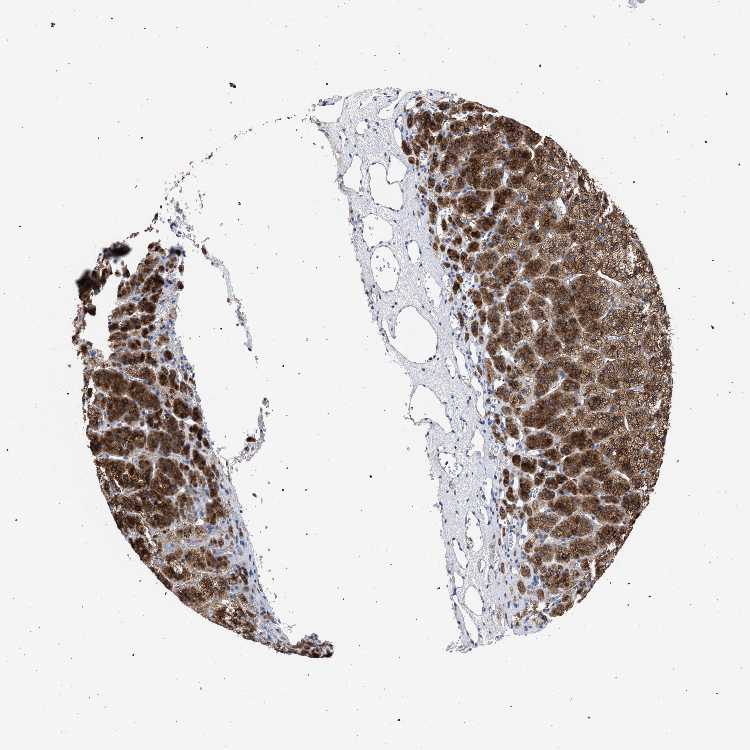

ADRENAL GLAND - Antibody stainingi

Antibody staining in the annotated cell types in the current human tissue is reported as not detected, low, medium, or high, based on conventional immunohistochemistry profiling in selected tissues. This score is based on the combination of the staining intensity and fraction of stained cells.

Each image is clickable and will lead to virtual microscopy that enables deeper exploration of all samples and also displays staining intensity scores, fraction scores and subcellular localization as well as patient and tissue information for each sample.

Antibody HPA000904Antibody HPA021476

Glandular cells HighHigh